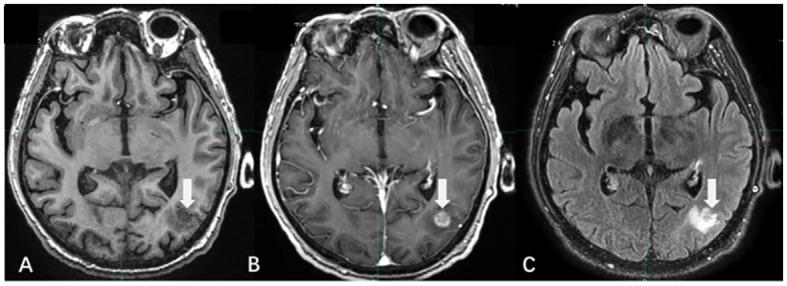

Brain metastases (BMs) are the most prevalent intracranial malignant tumors in adults and are the leading cause of mortality attributed to malignant brain diseases. Radiotherapy (RT) plays a critical role in the treatment of BMs, with local RT techniques such as stereotactic radiosurgery (SRS)/stereotactic body radiotherapy (SBRT) showing remarkable therapeutic effectiveness. The precise determination of gross tumor target volume (GTV) is crucial for ensuring the effectiveness of SRS/SBRT. Multimodal imaging techniques such as CT, MRI, and PET are extensively used for the diagnosis of BMs and GTV determination. With the development of functional imaging and artificial intelligence (AI) technology, there are more innovative ways to determine GTV for BMs, which significantly improve the accuracy and efficiency of the determination. This article provides an overview of the progress in GTV determination for RT in BMs.

脑转移瘤(BMs)是成人中最常见的颅内恶性肿瘤,也是恶性脑疾病致死的主要原因。放射治疗(RT)在BMs的治疗中起着关键作用,立体定向放射外科(SRS)/立体定向体部放疗(SBRT)等局部RT技术显示出显著的治疗效果。准确确定肿瘤大体靶体积(GTV)对于确保SRS/SBRT的有效性至关重要。CT、MRI和PET等多模态成像技术广泛用于BMs的诊断和GTV的确定。随着功能成像和人工智能(AI)技术的发展,有更多创新方法来确定BMs的GTV,这显著提高了确定的准确性和效率。本文概述了BMs放射治疗中GTV确定的进展。